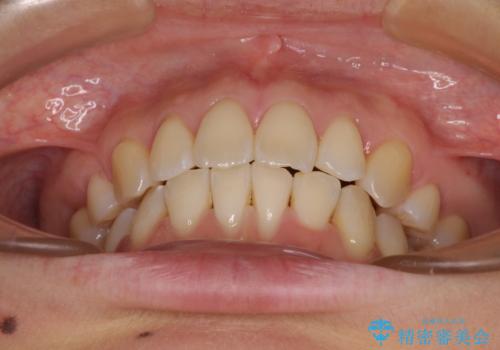

前歯のデコボコを抜歯矯正で改善 メタル装置で費用を抑える

- 前歯のデコボコと口元の突出感を気にして来院された患者様です。

非抜歯矯正ではデコボコを解消することでより口元が突出してしまうため、上下左右の小臼歯4本の抜歯を行い、ワイヤー装置による矯正治療を行うこととしました。

もう少し口元の突出感を改善したかったのですが、舌の突出癖が影響し下顎前歯が唇側に押させる仕上がりとなりました。